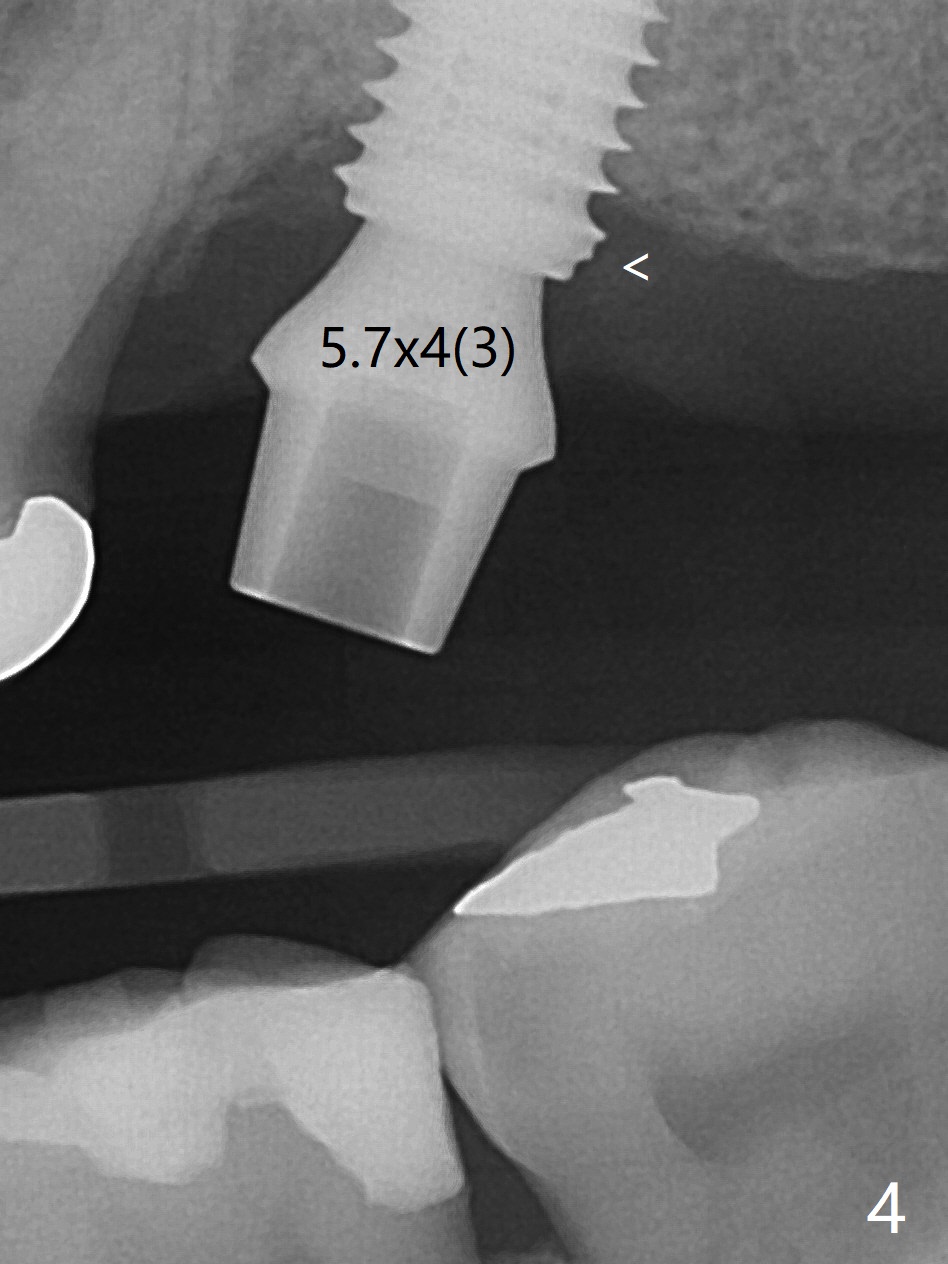

After extraction at #15 with 9 mm offset, a 12 mm bone trimmer is used to create a dimple in the septum. When a 4x7.3 mm drill is done according to drill sequence, initial osteotomy has no palatal wall. A 4.5x10 mm dummy implant cannot engage for sinus lift. DIO Sinus Approaching drill cannot enter IS green metal sleeve. When a 4x8.5 mm drill is finished, the sinus floor is intact. This is not the case when a 2.2x10 mm drill is used. Water membrane lifter does not seal the osteotomy (palatal defect). The 4.5x10 mm dummy implant is used for sinus lift, followed by 2-3 Amalgam carriers of allograft lifted with the same implant (Fig.1,2). After 4x10 mm drill and 2-3 carriers of Vanilla graft, a 5x11.5 mm implant is placed >55 Ncm with immediate placement of a 5.7x4(2) mm abutment (Fig.3). With sticky bone and 2 pieces of PRF in the remaining socket, an immediate provisional is fabricated and seated. When the patient returns for impression nearly 6 months postop, she feels mild pain. In fact the temporary crown/abutment is loose and traps food underneath with the erythematous gingival cuff. A 5.7x4(3) mm abutment is placed and torqued without gap for impression (no temp); the implant threads are exposed distal (Fig.4 <). Retrospectively, the incompletely seated cemented abutment should be tightened ~ 1 month postop when the socket heals.